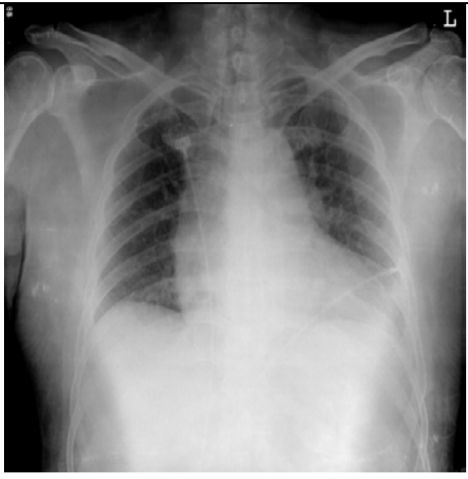

5. 病人男性59歲於午夜24時,突因胸悶並有牙床緊疼,乃直往急診部求診,時病人之T/P/R = 35.1/51/18, BP 137/74 mmHg; 理學檢查,未見任何異常。病史追尋,本病人曾經醫師確定高血壓、高脂血、糖尿病及攝護腺肥大,唯僅只服用Bisoprolol 2.5 mg/day。經緊急檢查:其心電圖及胸部X光顯示如圖:生化檢查: CK,96 U/L;CK-MB,20 U/L;TnI <0.0012 ng/ml;Sugar 252 mg/dL; Na,137 mmol/L; K, 3.7 mmol/L; TG,182 mg/dL and Total cholesterol, 222 mg/dL ; 血液檢查: Hb,13.9 g/dl; Platelet, 203 K/uL; WBC,9.45 K/uL; Cre,1.3 mg/dL 請問本病人最可能的急診診斷是:

(A) Printzmetal's angina (B) Aortic dissection (C) Acute anterior myocardial infarction (D) Hypertension (E) Acute periodontitis disease